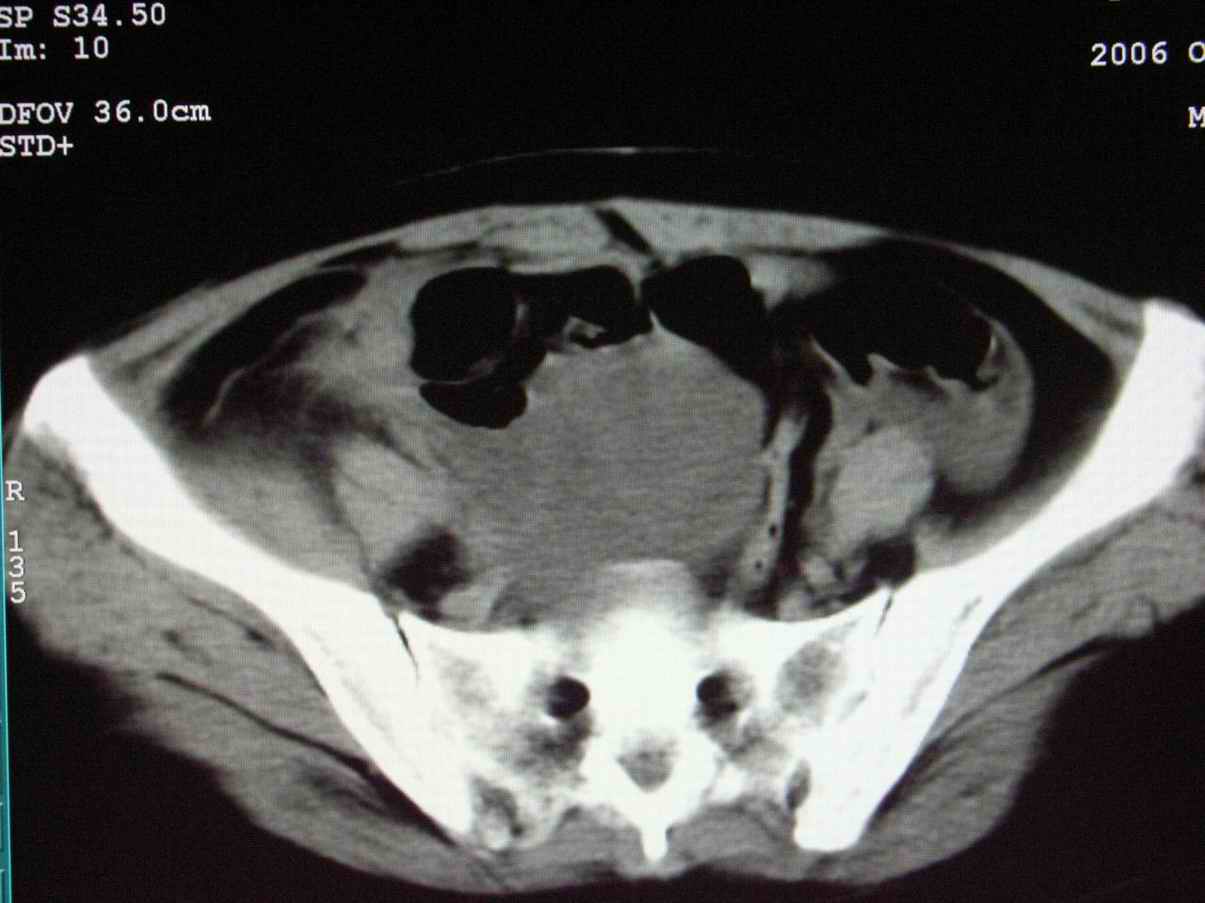

男;67岁,腹胀,腹痛,便血半年;钡餐透视发现右下腹部占位性病变

ct表现;病灶成环状软组织肿块,表现为不对称的肠壁增厚;肠腔变型.

支持结肠癌诊断,周围受累。